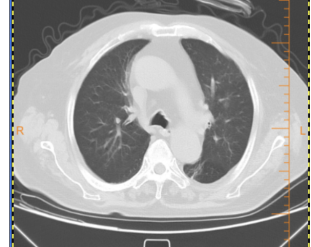

随访11-17胸部CT:

随访12-16胸部CT: